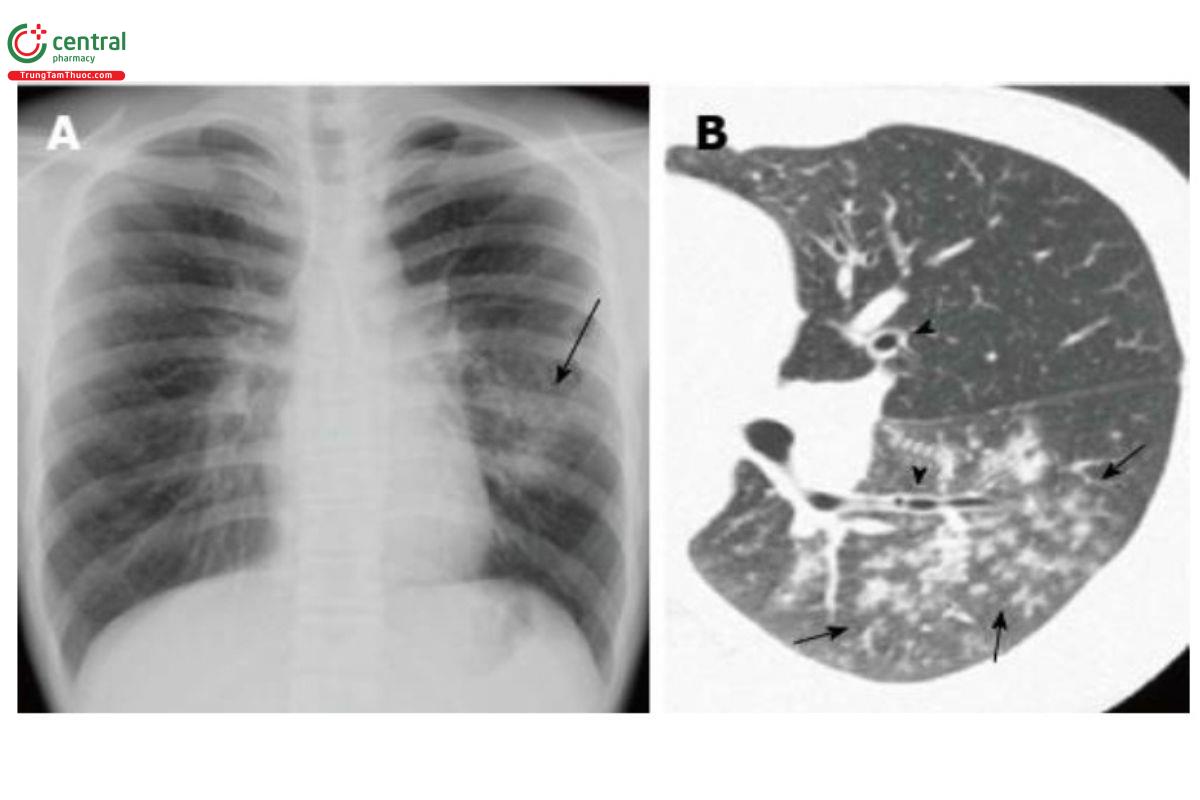

Tổn thương các nốt quanh phế quản chiếm ưu thế (Viêm phế quản - phổi): Tổn thương đặc trưng bởi các nốt trung tâm tiểu thùy có hoặc không có các đông đặc quanh phế quản [4,5]. Các đông đặc này có thể được hình thành do sự mở rộng và hợp nhất của các nốt quanh phế quản. Tổn thương thường đi kèm dày thành phế quản. Khi các nốt trung tâm tiểu thùy chiếm ưu thế, đặc biệt các tiểu phế quản và các vùng quanh tiểu phế quản bị ảnh hưởng chủ yếu, được gọi là viêm tiểu phế quản nhiễm trùng [4]. Tổn thương kiểu này thường gặp trong viêm phổi do Hemophilus influenzae, Mycoplasma pneumoniae, Chlamydophila pneumoniae, virus, lao và Non tuberculosis mycobacteria (NTM) [4].

A: X-quang ngực thấy các nốt, lưới mờ và đông đặc khư trú ở vùng giữa và dưới phổi trái (mũi tên). Rốn phổi trái to;

B: Trên CT thấy các nốt trung tâm tiểu thùy trên nền kính mờ ở thùy dưới phổi trái (mũi tên). Dày thành phế quản (đầu mũi tên)